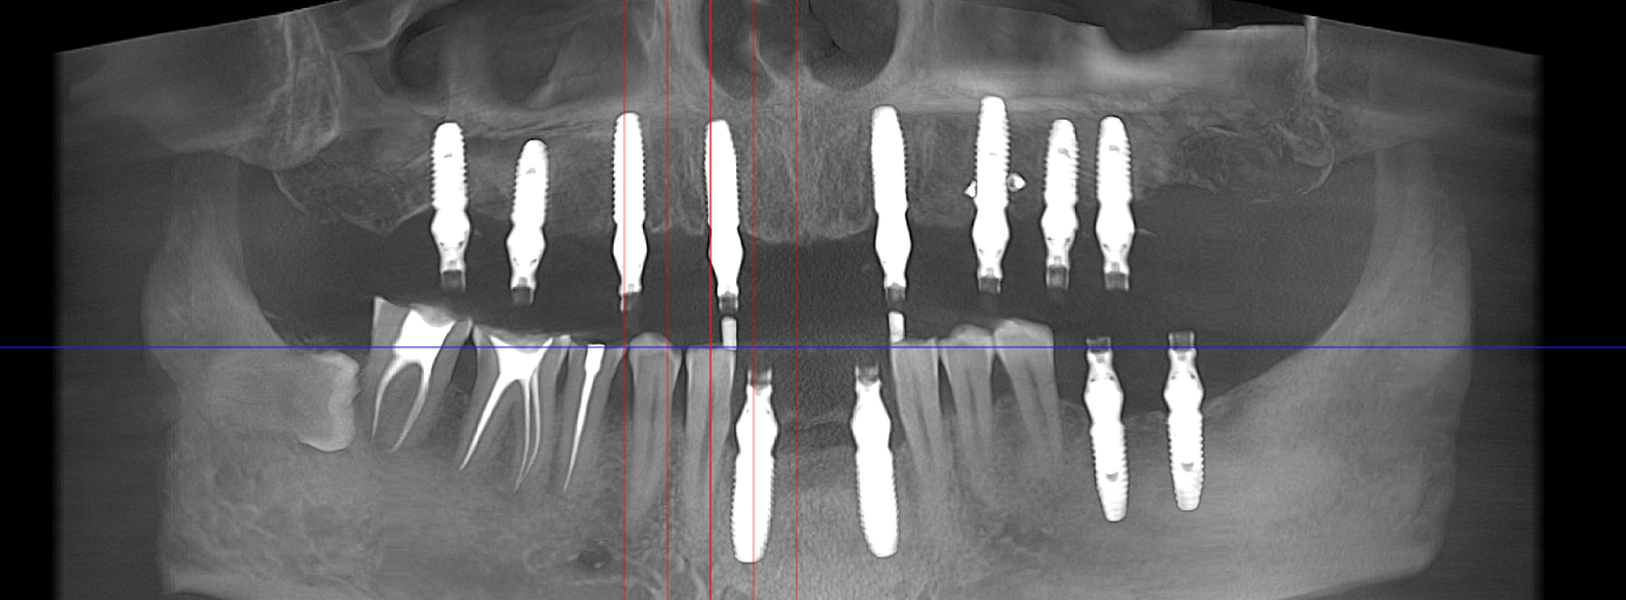

Tomografie (CBCT)

Caz 1

Caz 2